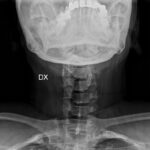

Le anomalie della colonna vertebrale sono frequenti nelle persone con pseudoacondroplasia e possono manifestarsi in diverse forme, contribuendo a dolore, rigidità e limitazioni funzionali.

Tra le principali alterazioni si osservano:

scoliosi, ovvero una curvatura laterale della colonna vertebrale a forma di “S”;

• iperlordosi lombare, caratterizzata da una curvatura eccessiva verso l’interno del tratto lombare;

• cifosi, una curvatura anomala della parte superiore della colonna vertebrale che provoca un arrotondamento accentuato della schiena.

Queste deformità possono peggiorare nel tempo e richiedono un attento monitoraggio clinico, oltre a interventi terapeutici e riabilitativi mirati.